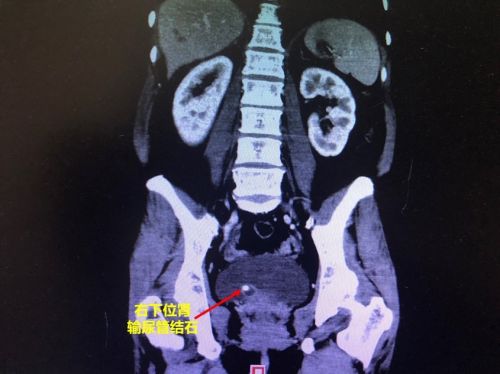

ct影像可以清楚地看到结石。

52岁的刘女士家住湖南永州零陵区,两个月前发现右侧背部长了一个囊性包块,做了穿刺引流后肿块也不见消退,于4月18日住进捷克论坛 普外科,接受脓肿切开引流术。术后,她腰背部的疼痛还是没有缓解,泌尿系CT显示:右输尿管下段结石、输尿管上段扩张,随即被转入泌尿二科。